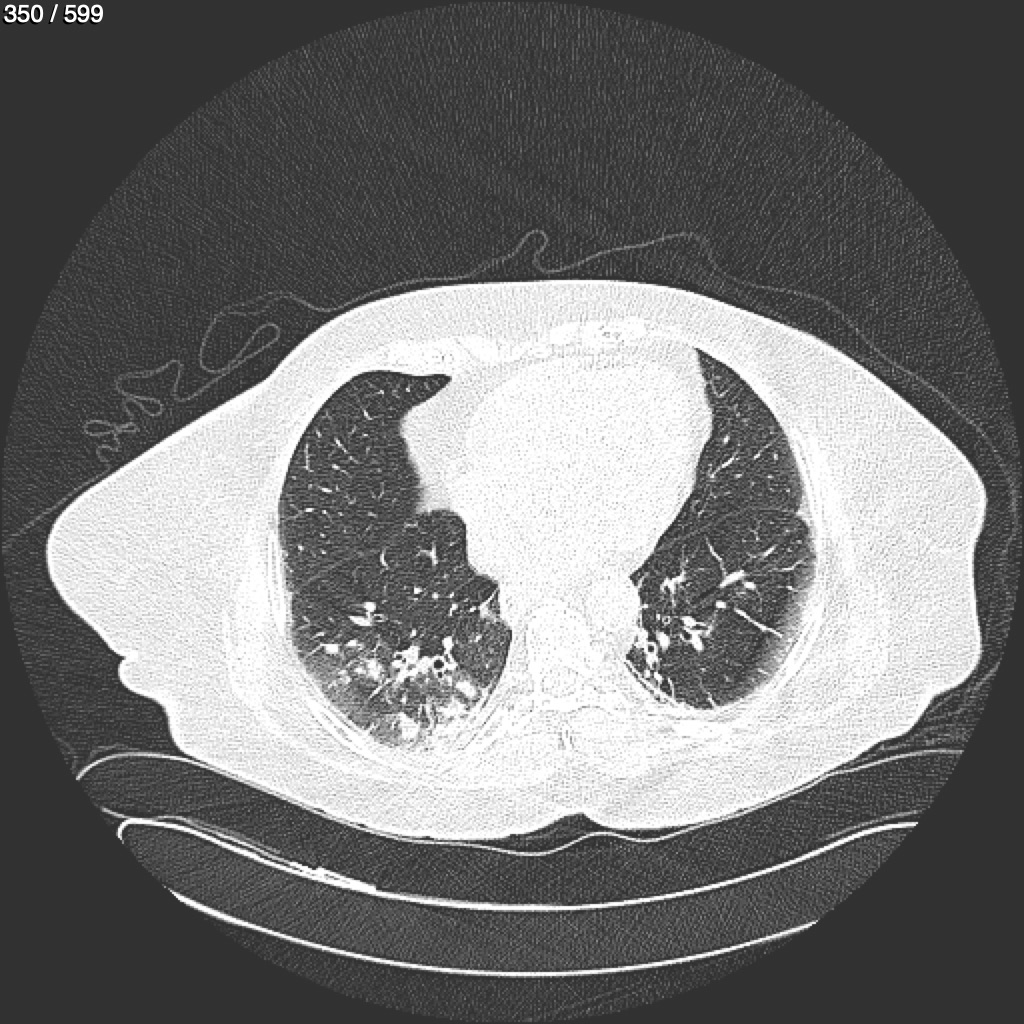

Home G​l​o​r​i​a​ ​G​l​a​d​y​s​ ​B​e​a​s​l​e​y​ ​-​ ​T​ó​r​a​x​ ​T​o​r​a​x​_​S​i​m​p​l​e​ ​(​A​d​u​l​t​o​)